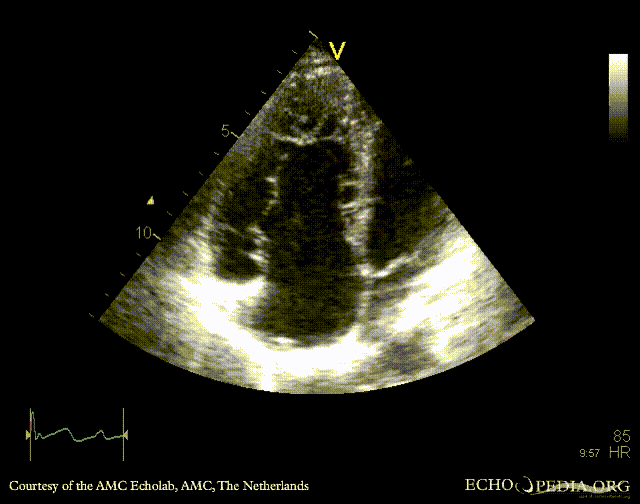

PLAX: enlarged right ventricle in patient with Ebstein anomaly A4CH: high insertion of tricuspid valve, enlarged right atrium and right ventricle